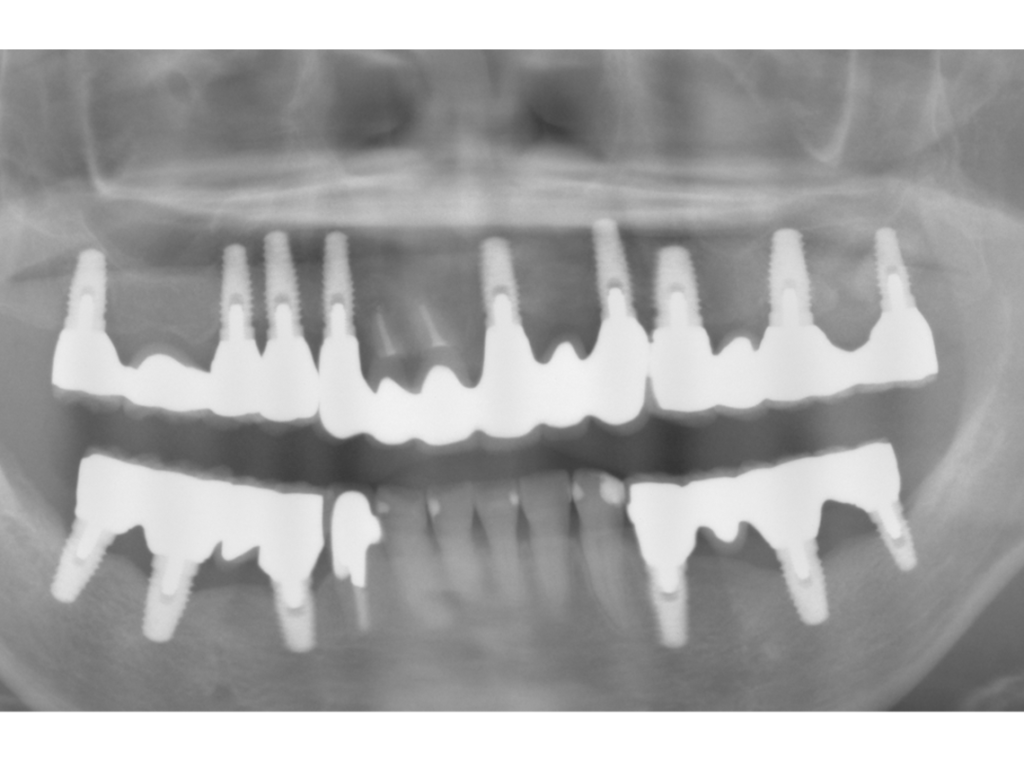

2008年8月27日撮影

2025年4月10日撮影

インプラント埋入部の骨レベルは埋入時と変わらず、患者様ご自身のメンテナンスも良好で、経過は非常に良く、満足されています。